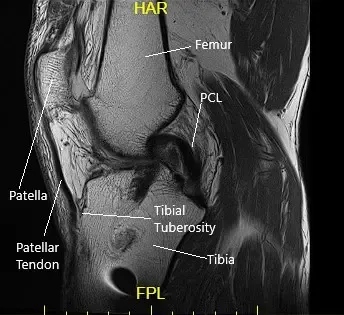

Le realizaron una resonancia magnética que mostró desgarros del menisco medial en la unión meniscocapsular y la unión posterior cuerno-cuerpo. Hubo pérdida de cartílago tricompartimental.

Vista de la rodilla izquierda por resonancia magnética sagital.